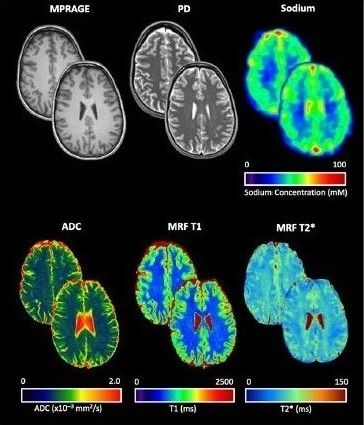

onlinelibrary.wiley.com/doi/full/10....

#neuroimaging #neurology #neuroskyence #radiology #syntheticmri #gadolinium #quantification

Free read

onlinelibrary.wiley.com/doi/full/10....

#neuroimaging #neurology #neuroskyence #radiology #syntheticmri #gadolinium #quantification

Free read